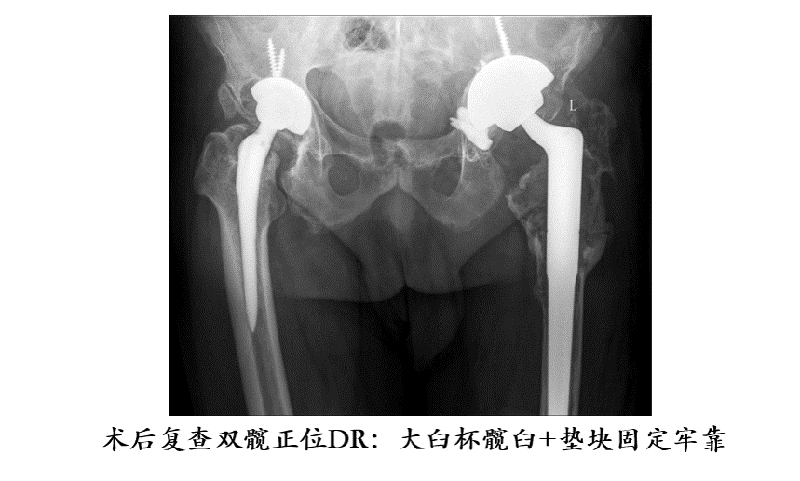

近日,河南理工大学第一附属医院骨科三区办公室内,在余进伟主任的指导下,由白伟医生主讲,全科医护成员围绕髋关节翻修,进行了从临床到护理,多角度深层次的学习和讨论,进一步提升医护人员的专业素养,打造以髋膝关节置换及运动医学为特色,以快速康复(Enhanced Recovery After Surgery, ERAS)及3D打印数字化骨科为先进理念的专业化团队,巩固了科室在焦作乃至豫北地区重要地位!